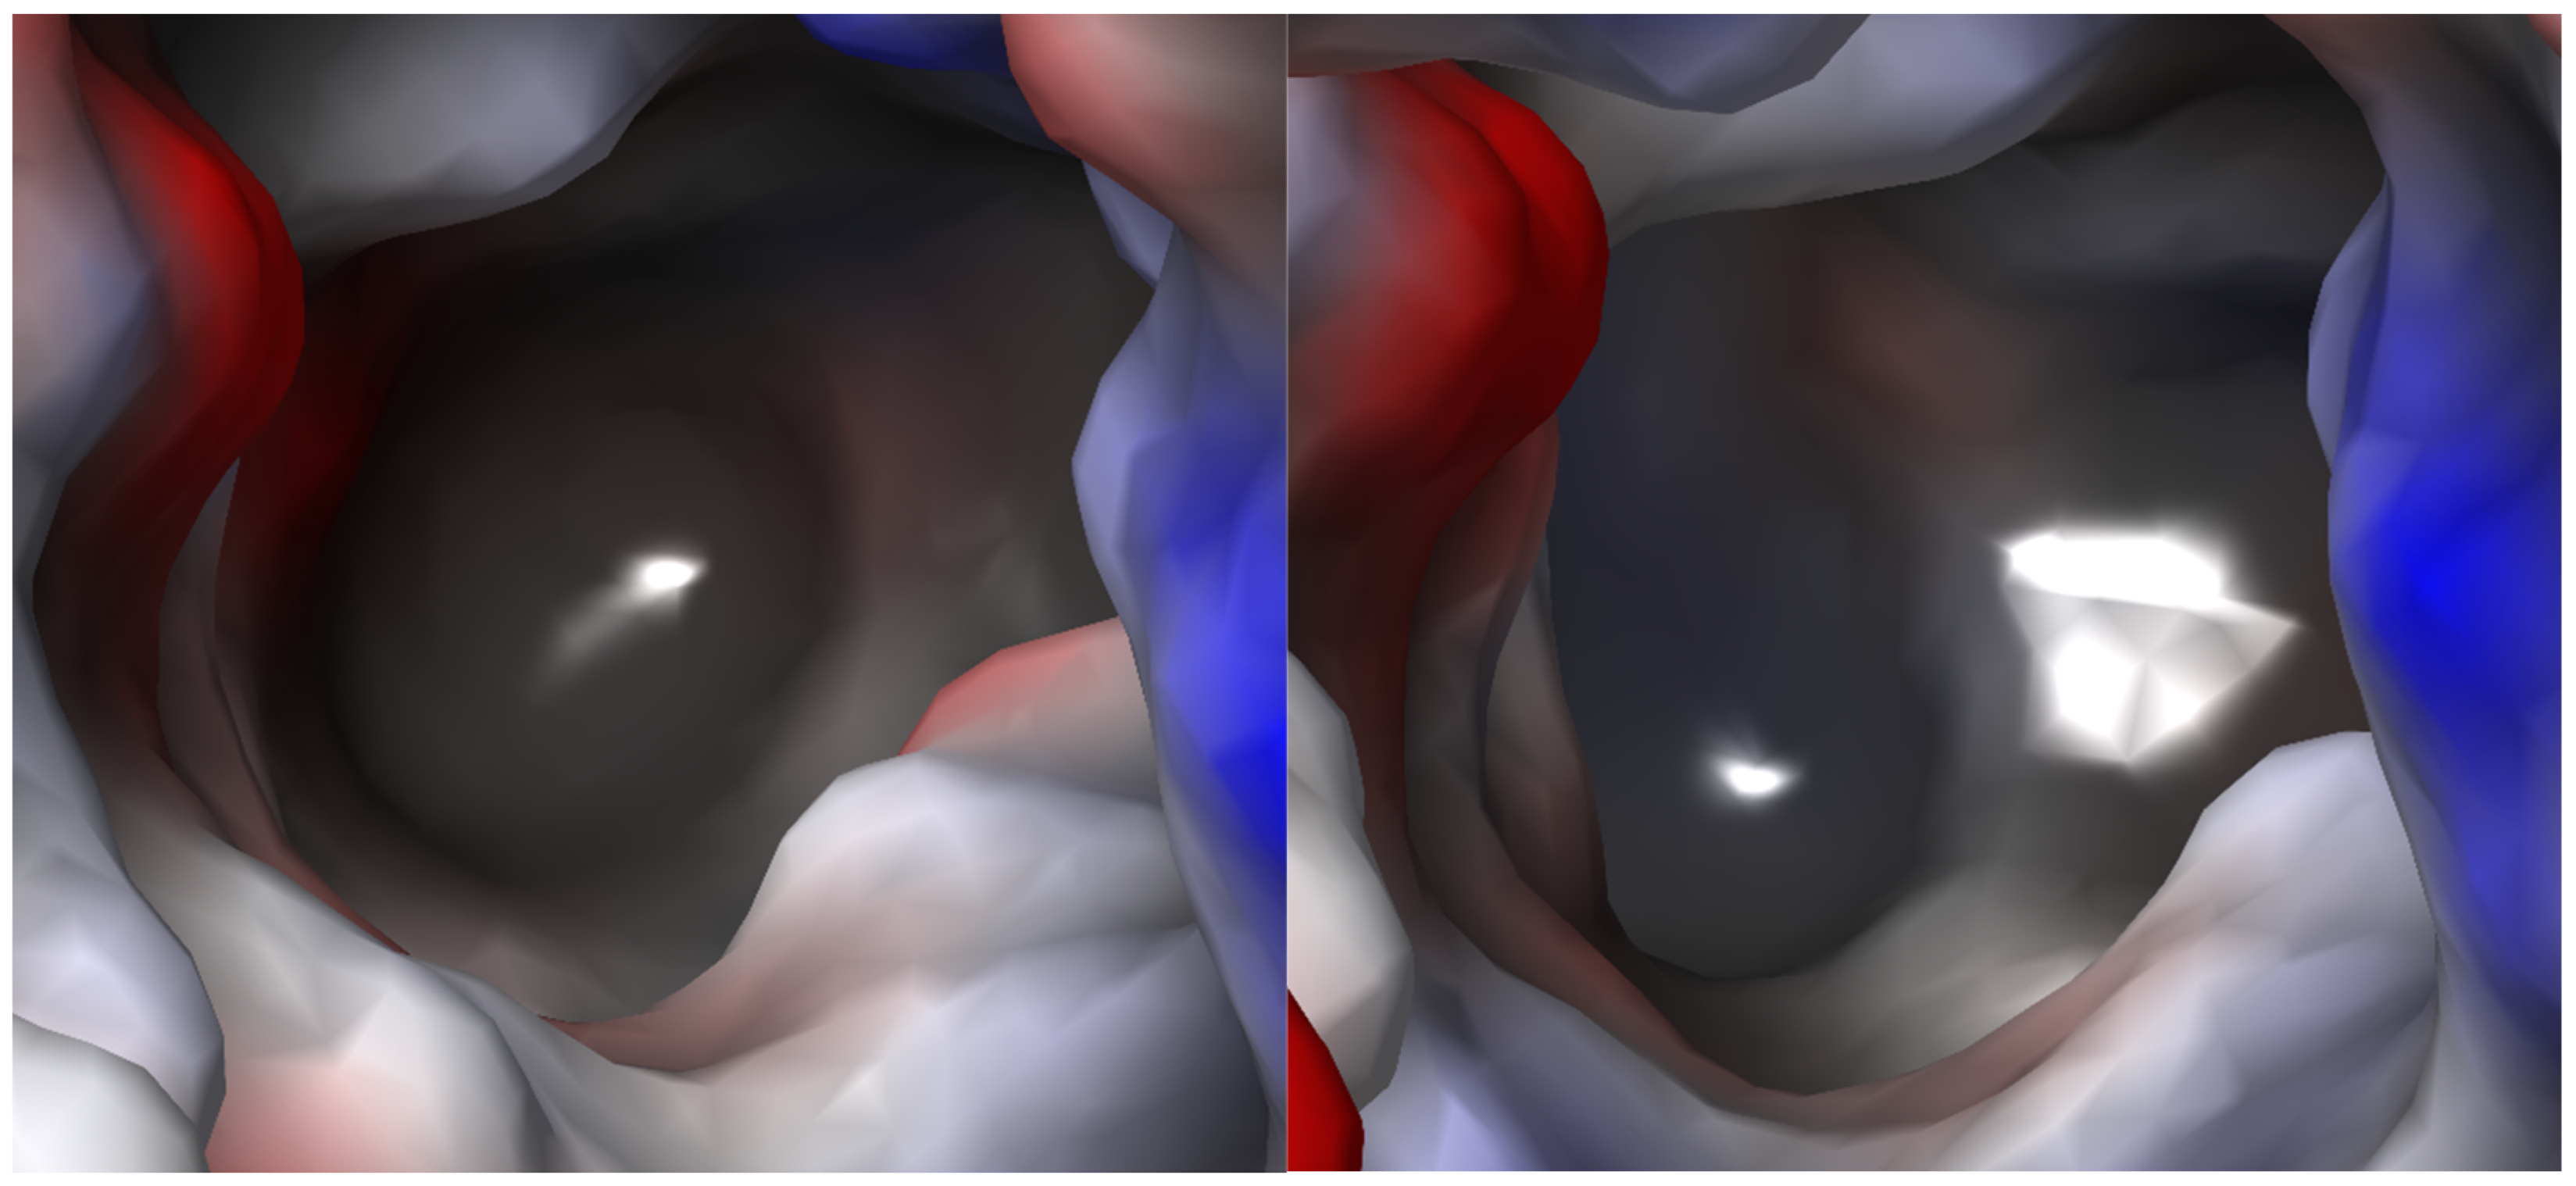

2.2.3. Binding Sites

2.2.4. S1 Binding Site Analysis